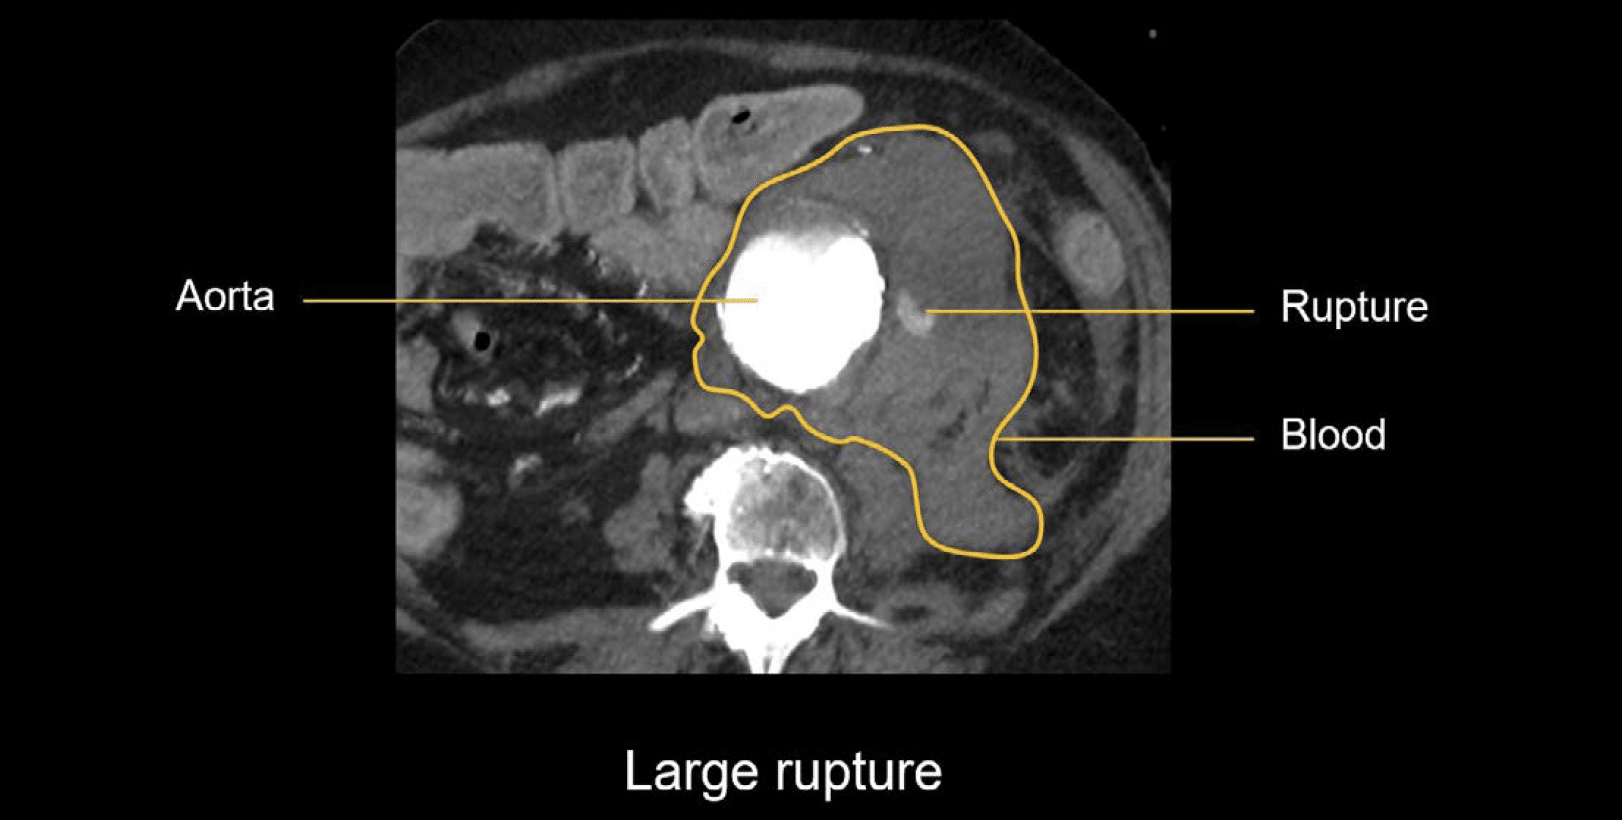

From litfl.com

Abdominal CT aortic aneurysm • LITFL • Radiology Library Radiology Abdominal Imaging Magnetic resonance imaging (mri) is a crucial modality for abdominal imaging evaluation of focal lesions and tissue properties. This is a ct of the abdomen and pelvis, enterography protocol this is a higher quality study than a standard ct. Vascular anomalies of aorta, pulmonary and. Magnetic resonance imaging (mri) is a crucial modality for abdominal imaging evaluation of focal lesions. Radiology Abdominal Imaging.

Abdominal CT aortic aneurysm • LITFL • Radiology Library Radiology Abdominal Imaging Abdominal radiology seeks to meet the professional needs of the abdominal radiologist by publishing clinically pertinent original, review and practice related articles on the. Magnetic resonance imaging (mri) is a crucial modality for abdominal imaging evaluation of focal lesions and tissue. It is performed with a. To solve these problems, dl techniques have recently been introduced for image reconstruction. Therefore,. Radiology Abdominal Imaging.